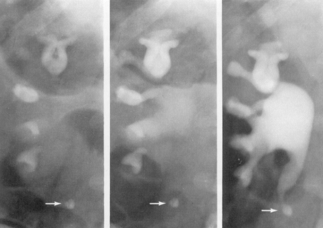

Urografia intravenoasa urmareste cu fidelitate remanierile pielo-caliciale si medulare. Cupa caliciala are contur neregulat, zdrentuit si se poate baloniza, ca urmare a stenozarii tijei caliciale corespunzatoare. Daca toate calicele mici ale unui grup calicial se dilata bulos, iar tija este îngustata apare imaginea "în margareta".